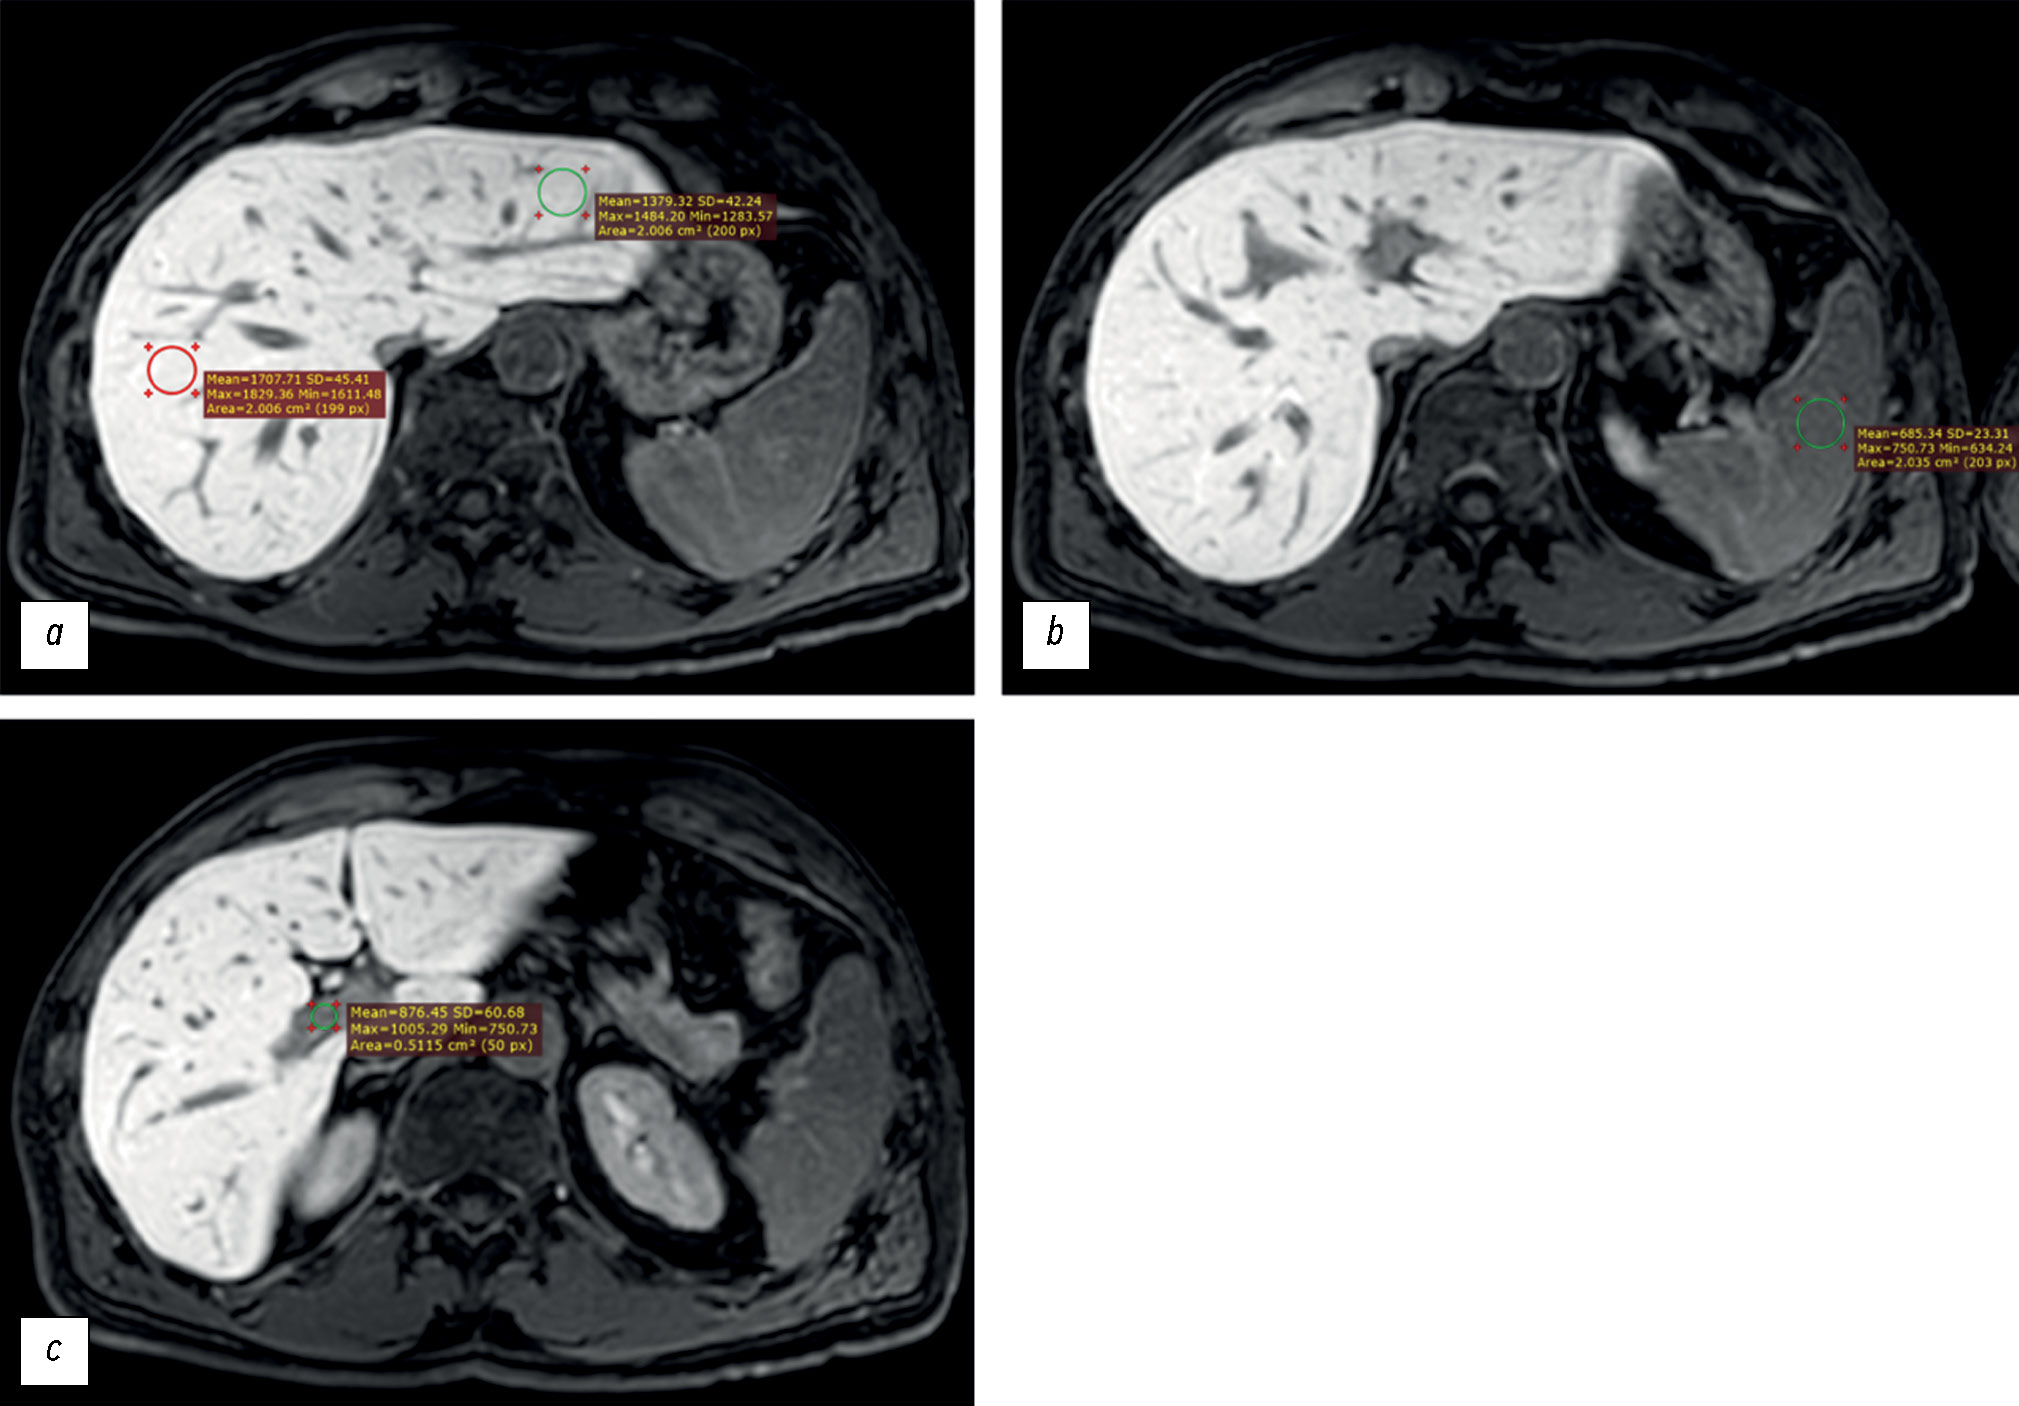

The signal intensity (in arbitrary units, au) was measured in the following regions of interest (ROIs, Fig. 1):

- Liver parenchyma (left and right lobes), outside the margins of the tumors, vessels, bile ducts and artifacts (if any) (ROI, at least 2 cm2 in diameter),

- Spleen parenchyma (ROI, at least 2 cm2 in diameter), and

- Lumen of the portal vein (ROI, at least 0.5 cm2 in diameter).

Fig. 1. Axial, T1-weighted, Gadoxetic acid–enhanced magnetic resonance imaging of the liver obtained 20 minutes after contrast administration. The signal intensity was measured in the following regions of interest: (a) right and left hepatic lobe parenchyma, (b) splenic parenchyma, and (c) portal vein lumen.